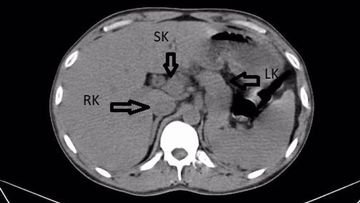

Dokter di India menemukan adanya ginjal ketiga pada pasiennya yang berusia 31 tahun. Begini penampakannya.